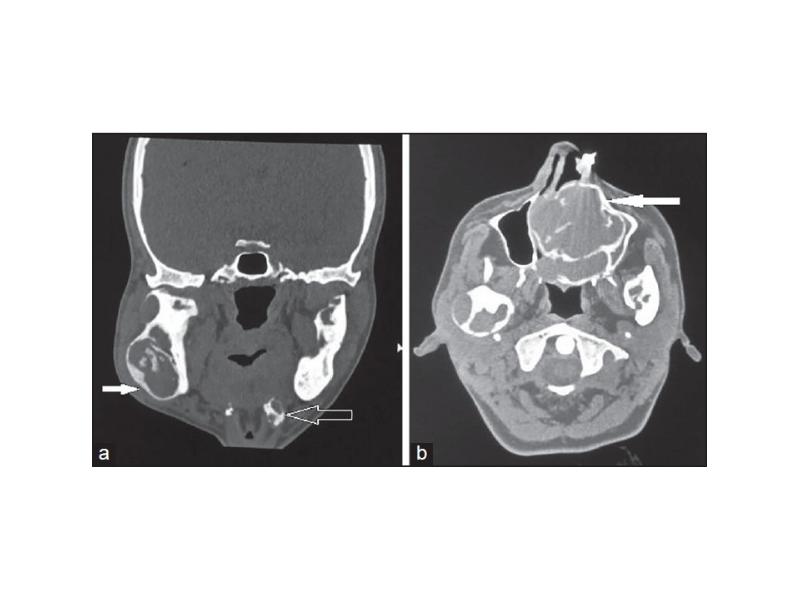

- 74. Центральная гигантоклеточная гранулема (остеокластома) До 30% всех опухолей челюстей и чаще

- 79. Исходы Различают агрессивные и неагрессивные гигантоклеточные гранулемы Агрессивные гранулемы, как правило,

- 80. Херувизм Редкое семейное заболевание (аутосомно-доминантный тип наследования), которое выявляется в раннем